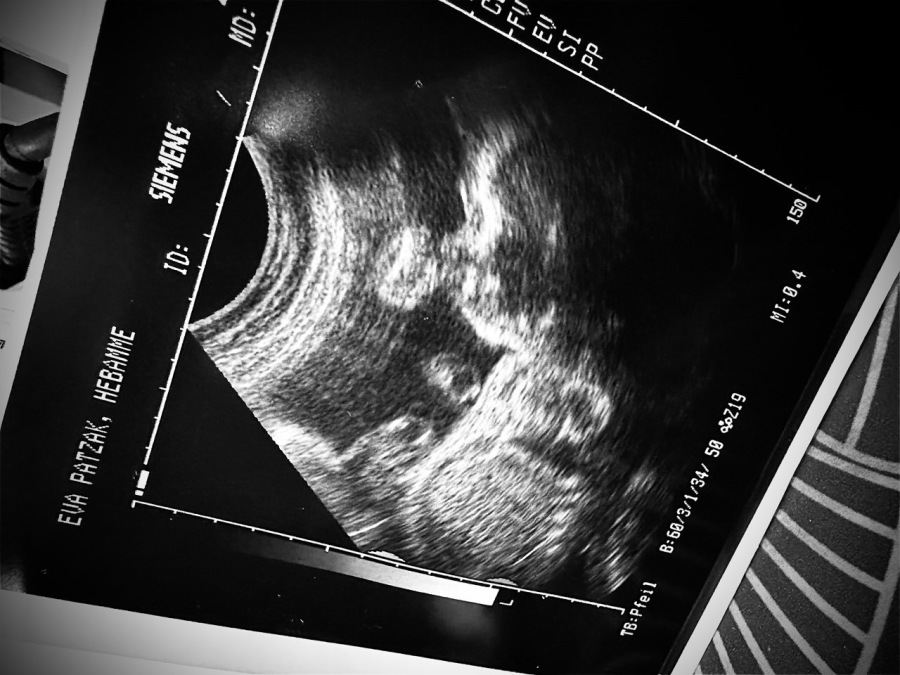

Hebammen und Ultraschall

Ultraschall in der Hebammenarbeit

Ultraschall ist ein bildgebendes Verfahren, das in bestimmten Situationen eine hilfreiche Ergänzung sein kann.

Durch Ultraschall lassen sich zum Beispiel die Lage des Kindes, die Fruchtwassermenge oder die kindliche Herzaktion manchmal eindeutiger beurteilen als nur mit den Händen.

Die Ultraschalluntersuchung ersetzt die manuellen Methoden nicht, sondern ergänzt sie sinnvoll.

So erhalte ich als Hebamme gemeinsam mit dir ein umfassenderes Bild vom Verlauf deiner Schwangerschaft und kann dich gezielt beraten.

Du profitierst vom Ultraschalleinsatz zum Beispiel bei:

• Unsicherheiten über die Kindslage

• Einschätzung der Fruchtwassermenge

• Sichtbarmachung der Herzaktion deines Babys

• Vorbereitung auf die Geburt, z. B. bei Hausgeburtsplanungen

Wichtig ist: Ich nutze Ultraschall nur im Rahmen einer normal verlaufenden Schwangerschaft und ausschließlich zur Orientierung. Die ausführliche Diagnostik (z. B. zum Ausschluss von Fehlbildungen oder bei auffälligen Befunden) übernimmt immer deine Ärztin oder dein Arzt.